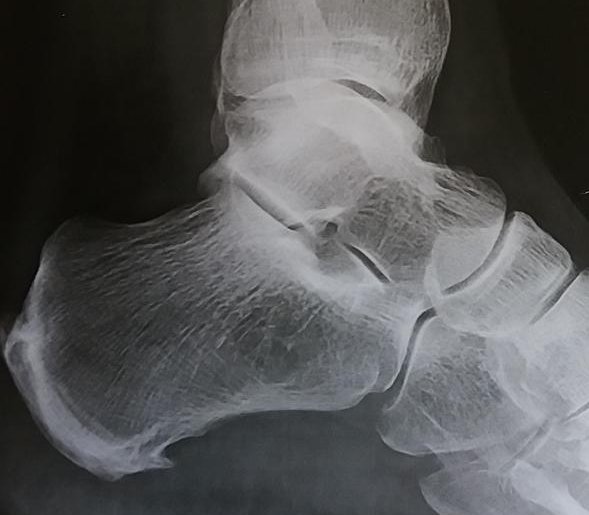

Fersensporn – wie er im Buche steht

Deutlicher ist direkt unterhalb ein Sporn zu sehen, ein sogenannter Fersensporn. Ein Fersensporn in dieser größer entwickelt sich über mehrere Wochen. Gründe gibt es viele wie: Fehlstellungen der Beine, X-bzw. O- Beine, Fehlstellungen der Füße bedingt durch chronische intestinale Krankheiten und Gangbilder, Überbelastung, falsches Schuhwerk… Bei der Patienten anbei spielt sicherlich der hauptsächlich stehende Beruf… Weiterlesen Fersensporn – wie er im Buche steht